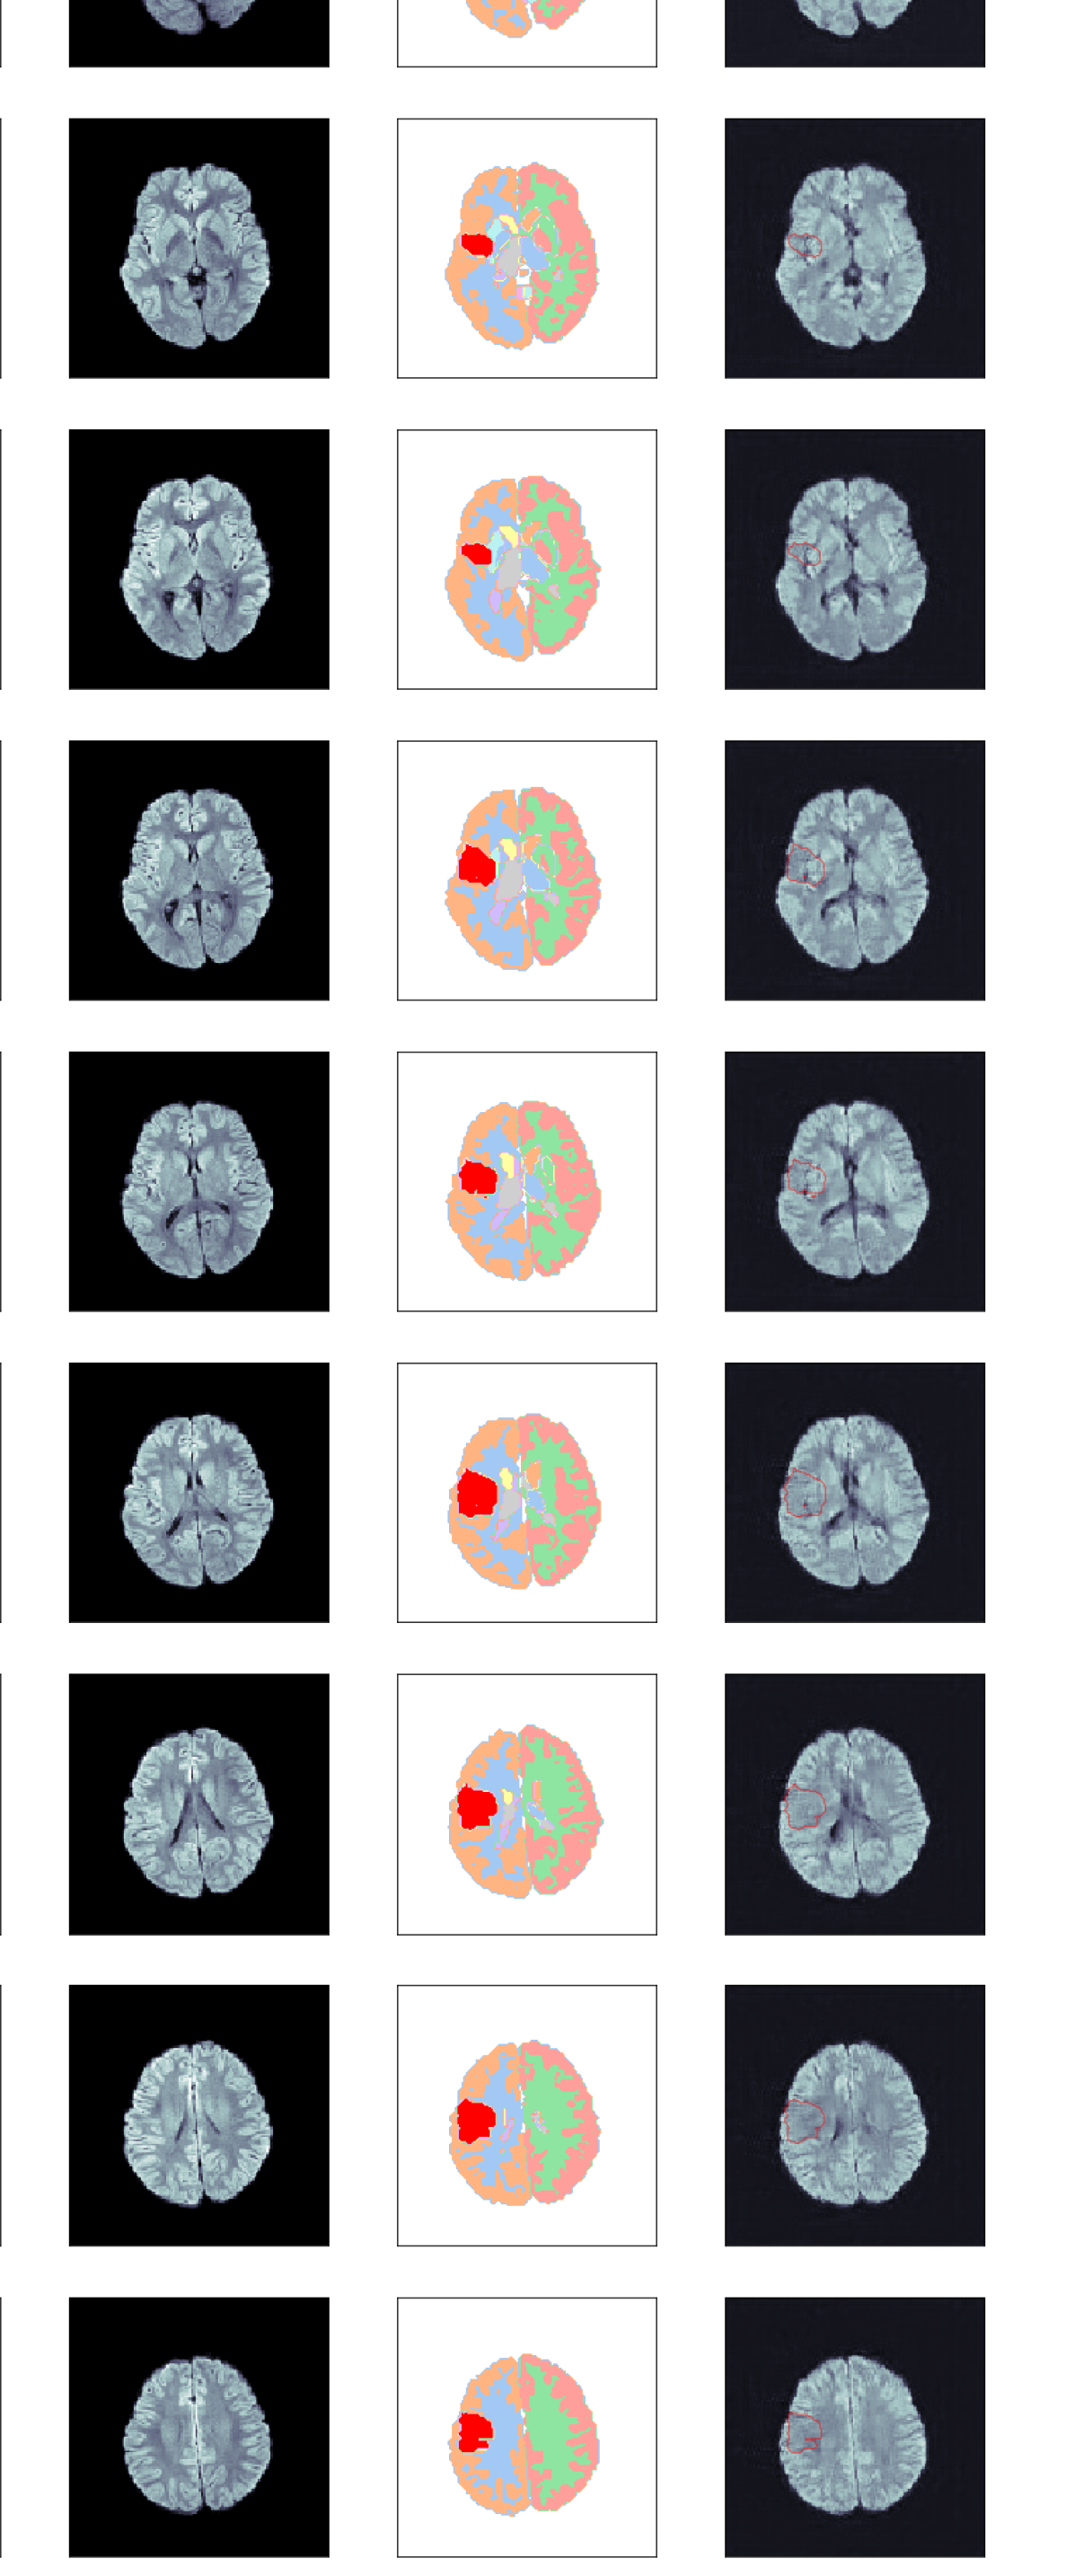

The generated segmentation map is subsequently decomposed into 2D slices and fed into the ITM in order to generate a fake DWI. In this manner we obtain a database of 2027 fake DWIs per ITM. Fig. 2 shows an example of this lesion implantation procedure, which is also sketched in the graphical abstract. The left column shows the healthy input DWI volume, whose corresponding semantic segmentation map is shown next to it. The third column shows the segmentation map after implanting a lesion label according to the output of the GAN. Subsequently, we have generated realistic DWIs from axial slices of these 3D segmentation maps using three ITMs, namely Pix2Pix, SPADE and cycleGAN, as shown in the right-most column for one axial slice.

Fig. 4 shows some examples of generated images. The synthetic DWIs generated by the ITMs display anatomical structures that are coherent in location, shape, and size across the volume, including the lesions. The first two images from the left have been generated using Pix2Pix. Panel (a) was generated using a reconstruction loss weight , while Panel (b) was created using . The results are of good quality, subjectively realistic and, as anticipated, come accompanied by a high-fidelity lesion label. Only closer inspection of a number of volumes reveals that the larger reconstruction loss weight produces slightly sharper images with more details both inside the lesion and in the brain tissue. We have therefore tested both models quantitatively in the following section.

The lesion intensity produced by SPADE [Fig. 4(c)] is noticeably lower than in the images generated by Pix2Pix, but also the contrast outside the lesion is much lower: in the posterior part of the synthetic brain, barely any gray/white matter contrast is present. While this might seem a disadvantage at first sight, it could actually be beneficial for training a U-Net to reliably detect lesions with lower signal increase.

Next, notice that cycleGAN has failed to recognize and synthesize any lesion hyper-intensity, while producing very high inter-tissue contrast [Fig. 4(d)]. We have experimented with fine-tuning the model on IS data, training on IS data alone, and modifying the network architecture; however, this result seems to be unavoidable. We speculate that this is closely related to the cycle consistency requirement of cycleGAN, i.e. that the two generators map an image back to itself as close as possible, and large class imbalance between lesion and non-lesion voxels. Similarly, Ref. cycleGAN identified ‘failed cases’ which indicate that cycleGAN generalizes poorly. Due to this failure, we have excluded cycleGAN from the quantitative analysis, and leave a dedicated study using cycleGAN for data augmentation for future work. We stress that this does not preclude any application of cycleGAN to this task; however, it will require an approach that differs from the one chosen here, and thus the comparability of ITMs is not given.